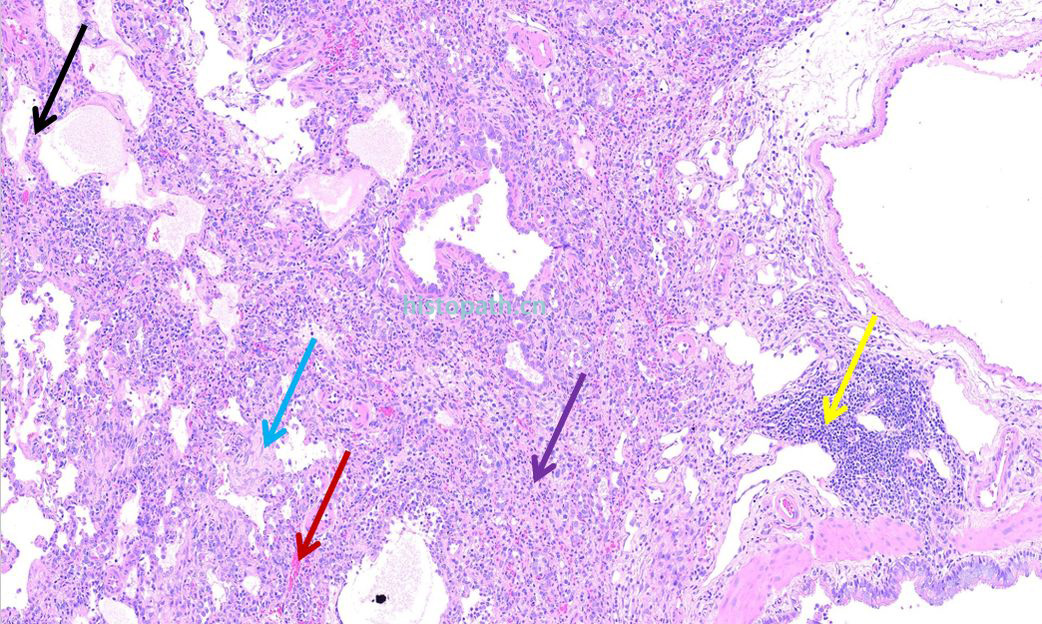

结果分析:HE染色可见肺组织炎症性改变:肺泡隔增厚(黑色箭头),局部肺组织结构破坏(紫色箭头),血管扩张充血(红色箭头),间质纤维组织增生(蓝色箭头),伴大量炎性细胞浸润(黄色箭头)。